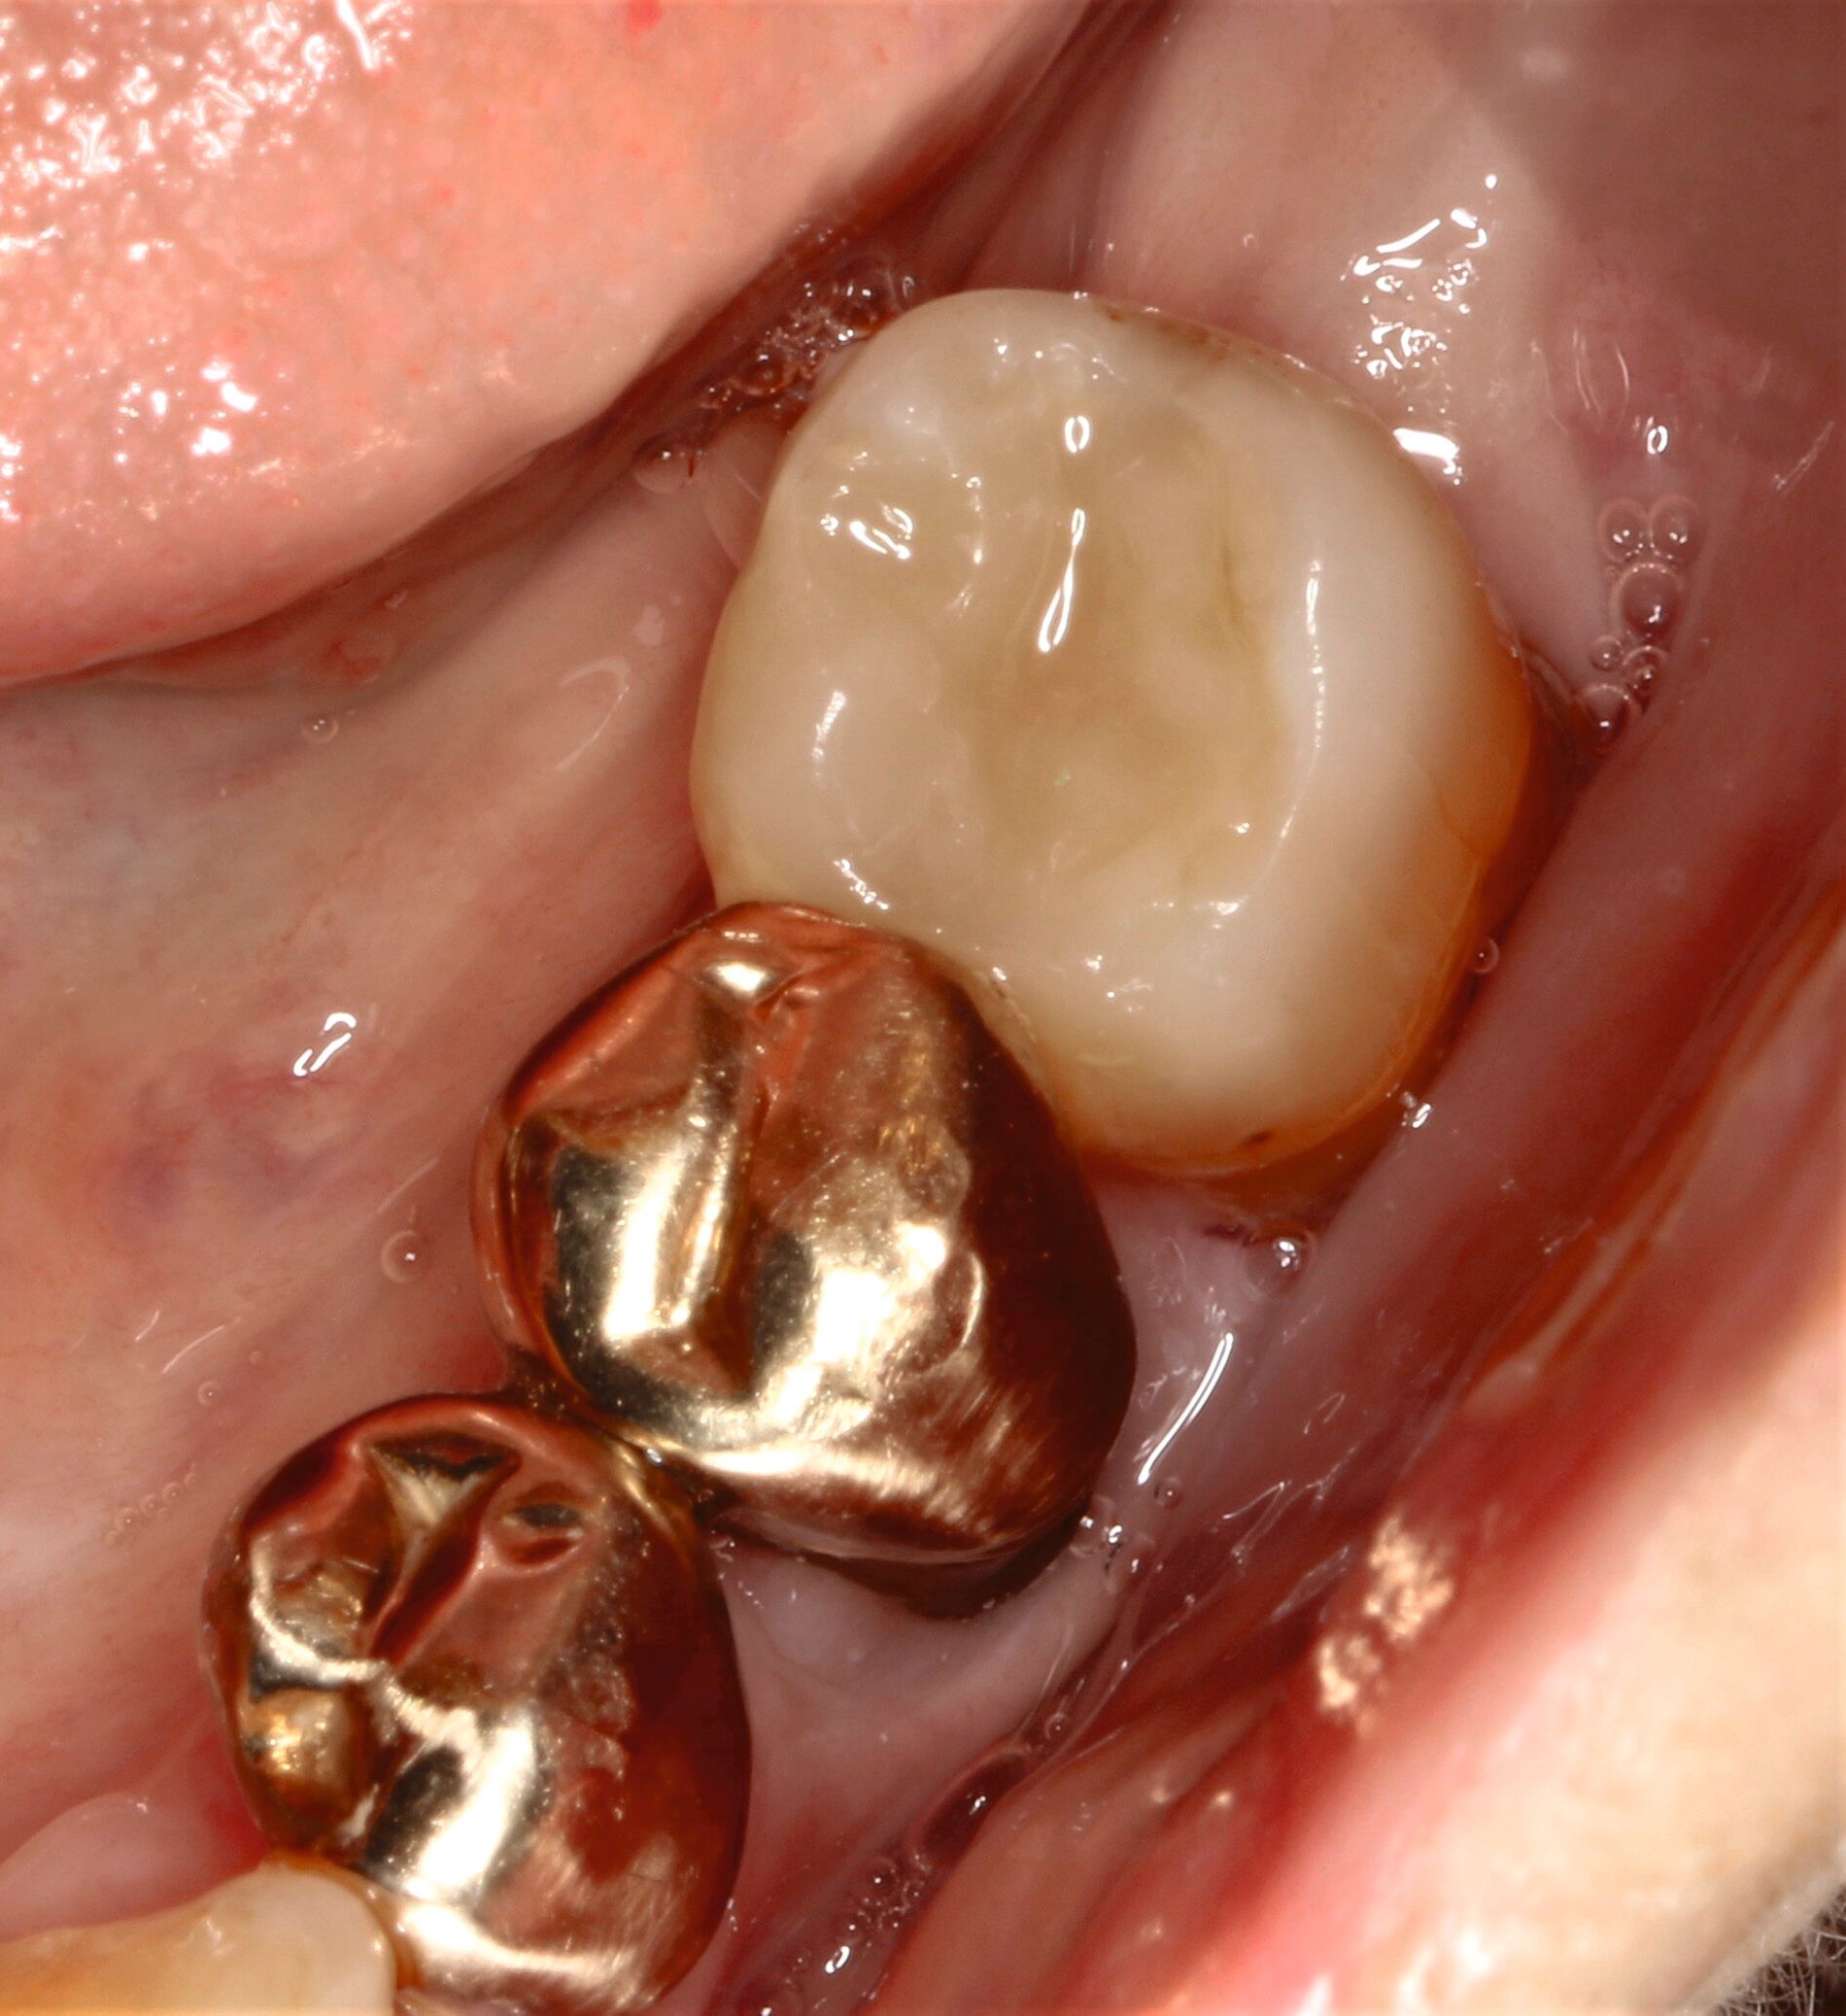

Die von ihr als störend empfundene scharfkantige Füllungsfraktur konnte noch am selben Tag mit einer direkten Kompositrestauration (Reparaturrestauration unter Verwendung des Cojet-Systems, 3M Espe; Monobond Plus, Ivoclar; Optibond FL Adhäsiv, Kerr; Ceram X Spectra STHV, Dentsply Sirona) versorgt werden. Nach der weiteren Befunderhebung und der Empfehlung zur Wiederaufnahme der UPT wurde die Patientin über eine parodontale Schienungsmöglichkeit der Unterkieferfrontzähne aufgeklärt, die ihr an einem Folgetermin samt UPT wenige Wochen später angeboten wurde.